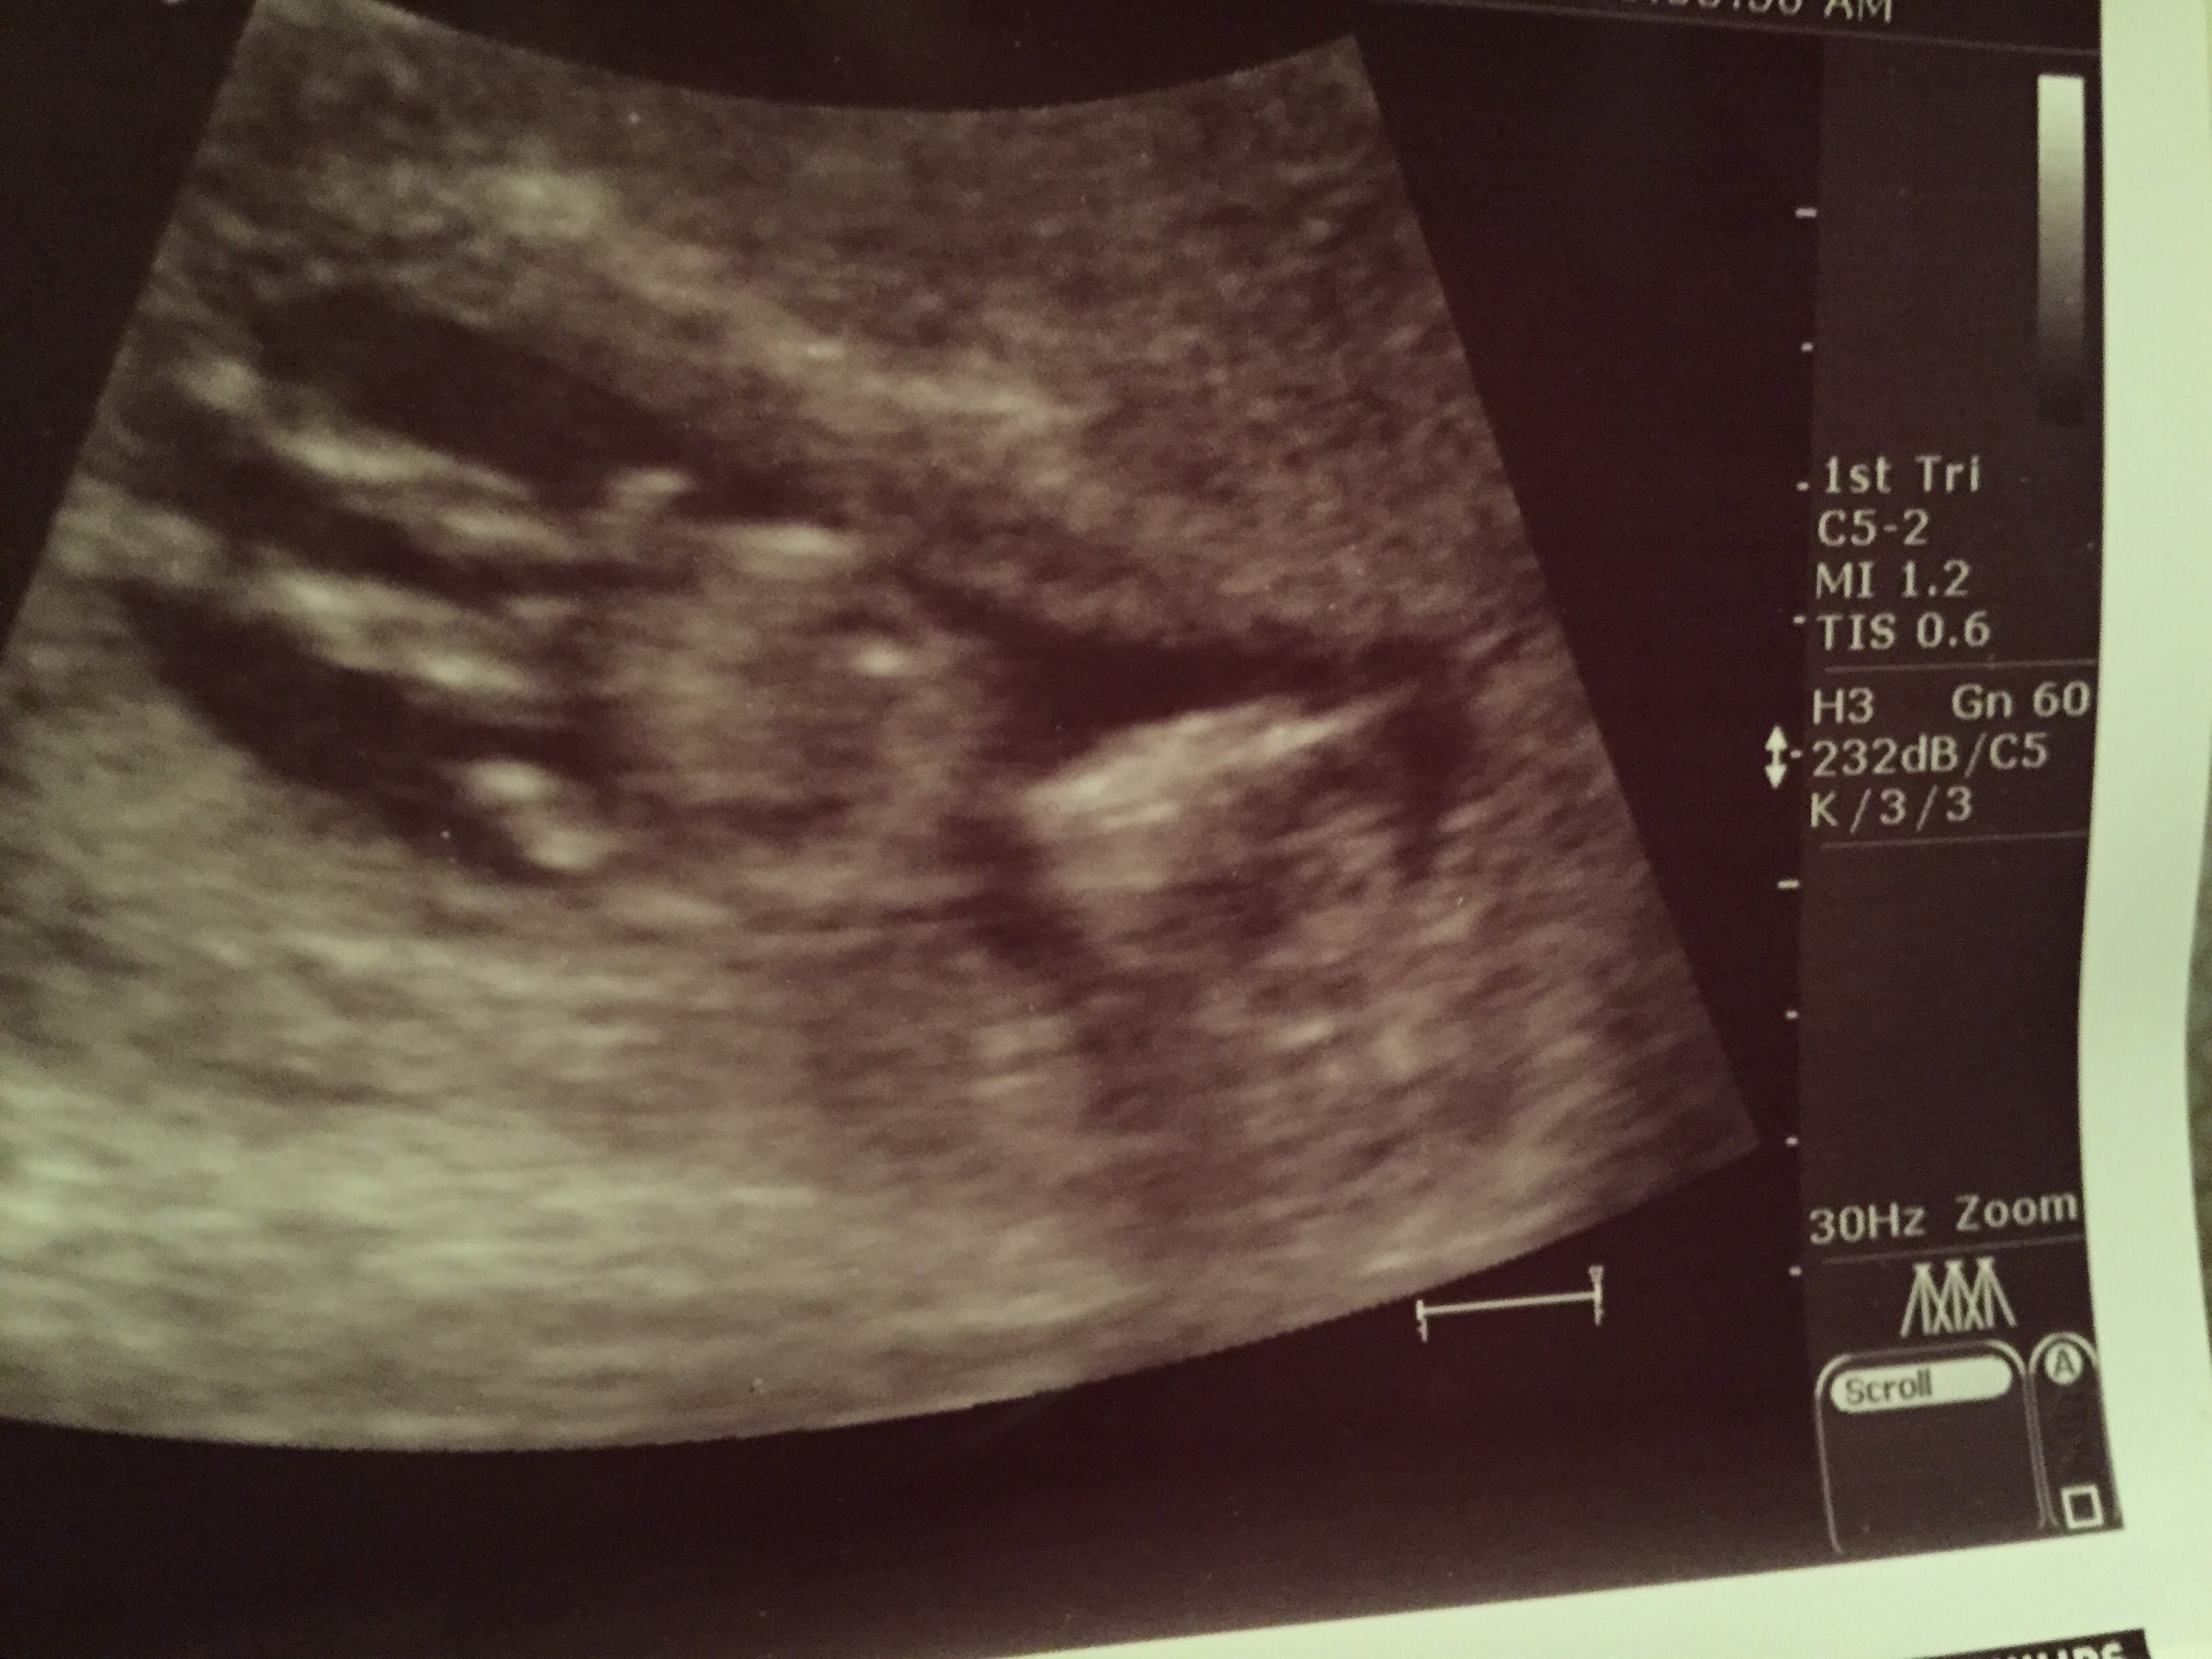

ddecile said: What do u guys think????

Re: Boy or Girl

Or maybe a boy.